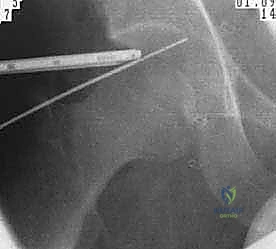

يتم غالباً استخدام التخدير العام أو النصفي. يوضع المريض على طاولة عمليات خاصة تُسمى (Traction Table). يتم سحب الساق برفق شديد لفتح مسافة صغيرة جداً في مفصل الورك (حوالي 1 سم) تسمح بإدخال الكاميرا والأدوات الجراحية بأمان دون إتلاف الغضروف.

2. إحداث الشقوق وإدخال الكاميرا

يتم عمل شقين أو ثلاثة شقوق صغيرة. يُضخ سائل معقم داخل المفصل لتوسيعه وغسل أي بقايا، ثم يتم إدخال كاميرا الألياف الضوئية (Arthroscopy) التي تنقل صورة مكبرة وعالية الدقة (4K) إلى شاشات العرض.

3. تقييم الضرر والإصلاح

بناءً على التشخيص المسبق والرؤية المباشرة، يبدأ الجراح في العمل:

* إذا كان هناك تمزق في الشفا، يتم استخدام أجهزة خياطة دقيقة لتثبيته.

* إذا كان هناك اصطدام عظمي (FAI)، يتم استخدام جهاز حفر ميكروسكوبي (Shaver/Burr) لنحت العظم الزائد وإعادة تشكيله.